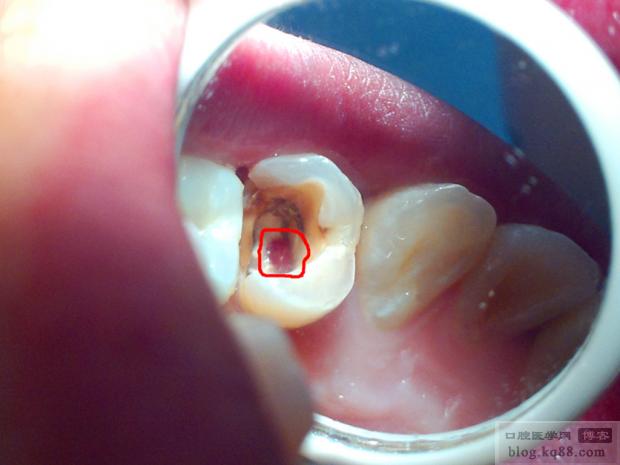

我的牙齿有侧穿或者低穿吗

意见,图片是我自己拍的不是很清楚大家将就着看吧, 这个牙齿是牙痛在